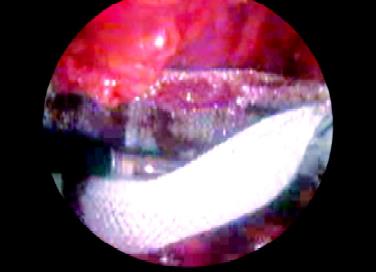

The technique of insertion of mesh in the totally extraperitoneal repair of a hernia is the same as that of transabdominal preperitoneal. Mesh of the appropriate size usually 15 × 15 cm is used and rolled and loaded backward in one of the port. Mesh should be fixed by stapling first in its middle part three-finger above the superior limit of the internal ring. In totally extraperitoneal repair some surgeon does not use a staple, because peritoneum is not breached and once the gas from preperitoneal space is removed, it will place the mesh in its proper position. In 1 to 2 percent of cases of TEP conversion to open or TAPP may be necessary due to large peritoneal tear making the vision difficult or in the cases where content is not reduced completely.

Introduction of mesh

Placement of mesh